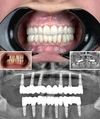

Diş Eksikliği

Periimplantitis